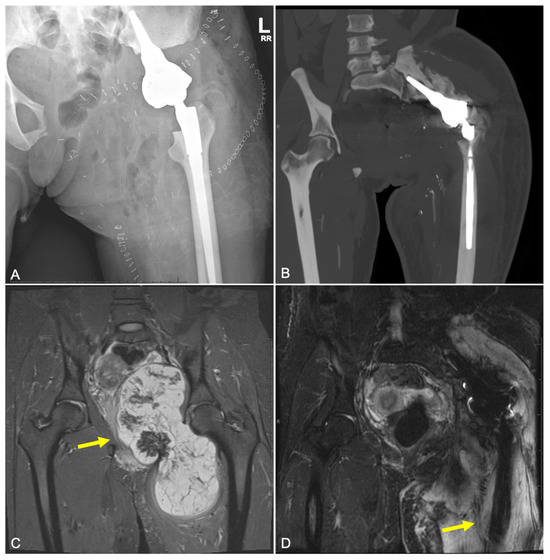

2.2. Type 2 Failures—Loosening and Nonunion

2.2.1. Endoprosthetic Aseptic Loosening

2.3. Type 3 Failures—Structural

2.4. Type 4 Failures—Infection